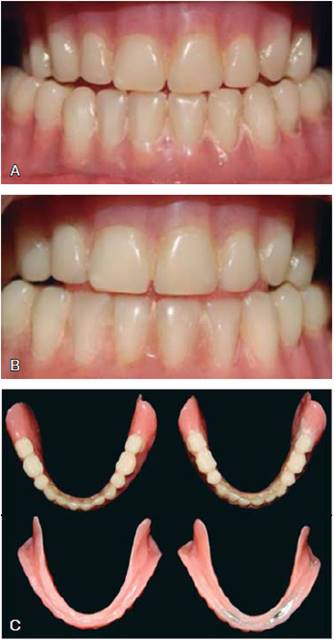

Se llevó a cabo un ensayo clínico cruzado (con el sujeto como su propio control). Se realizó un muestreo de conveniencia seleccionando a los sujetos de la Clínica de Prostodoncia Total de la Facultad de Odontología, UNAM, totalmente desdentados con una clasificación del reborde residual V o VI según Cawood y Howell (1988), con una altura no mayor a 2 mm, en un rango de edad de 55 a 85 años, sin patologías mentales y controlados sistémicamente (Figuras 1 y 2). Fueron evaluados inicialmente apreciando la actitud mental House Boucher.2 A todos los pacientes seleccionados se les invitó a participar en la investigación, los sujetos que aceptaron lo realizaron bajo consentimiento válidamente informado. Se realizó el procedimiento clínico, dividiendo en dos grupos a los sujetos. El grupo 1 fue designado a utilizar inicialmente las PC, el grupo 2 a utilizar inicialmente las PG. Para ambos se estableció un periodo de uso de seis meses, realizando los ajustes requeridos, así como dando indicaciones por escrito. Después se duplicaron las prótesis inferiores impresionando a boca cerrada, para después cambiar de grupo (diseño cruzado) (Figura 3).

Figura 3 Prótesis total inferior convencional y gravitacional, ambas idénticas. A) Convencional. B) Gravitacional. C) Comparación de ambas prótesis.